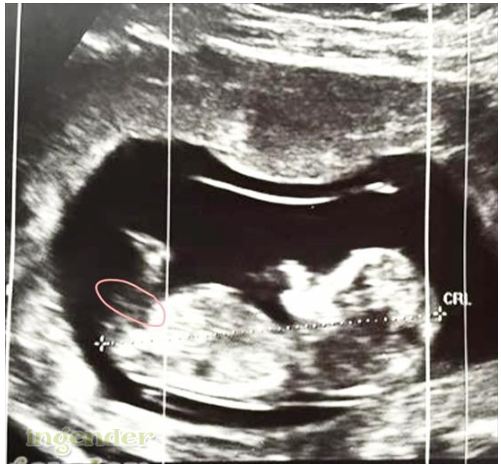

At my 12 weeks ultrasound, doctor advised this is girl. But a lot of inputs the nub look boyish. Anyone have any ideas?Attachment 24016

The nub is VERY distorted from movement. I see why you get boy guesses because it appears at an angle, but its not where it should be its practically coming out of the stomach because of the distortion.

One suggested this is where baby nub is positioned. Should it be correct? Thankssss